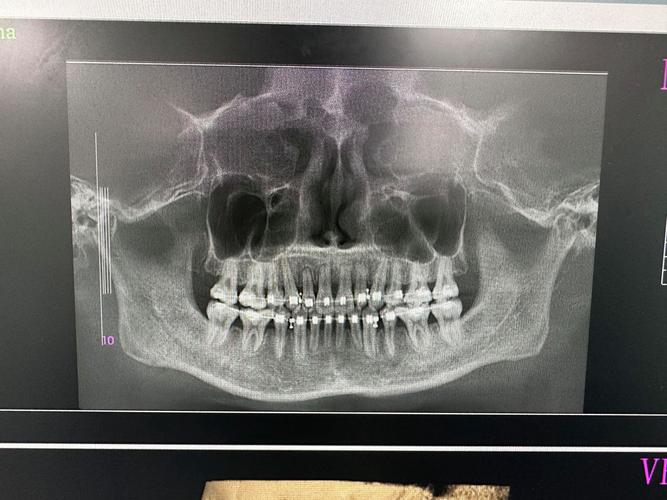

全景片(曲面断层片):牙齿与牙槽骨的“全景地图”

全景片是正畸复查中最基础的影像,能一次性展示全口牙齿、牙根、牙槽骨、颌骨及牙周组织的整体情况,三个月时,医生重点关注以下内容:

- 牙根状态:观察牙根是否平行、有无吸收(牙根尖端变短或模糊),轻微牙根吸收在正畸中较常见,但若吸收明显需调整矫治力;若牙根周围暗影(牙槽骨)密度均匀增高,提示牙槽骨改建活跃,牙齿移动健康。

- 牙齿移动度:对比初诊片子,看目标牙齿(如拥挤的切牙、扭转的后牙)是否向设计方向移动,上颌前牙若存在拥挤,三个月时应看到牙冠向唇侧或远中倾斜,牙根向腭侧移动的迹象。

- 第三磨牙(智齿)位置:若患者有未萌出的智齿,全景片可观察其牙胚方向与第二磨牙的关系,判断是否影响后牙移动或需提前拔除。